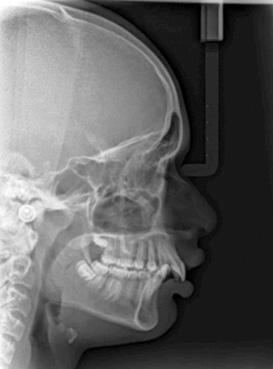

Panoramic radiogram revealed a complete permanent dentition with four impacted wisdom teeth. There was excellent bone support and no signs of periodontal or periapical pathology (Figure 5-A).

Fig. 5-A: Pre-treatment, panoramic radiogram